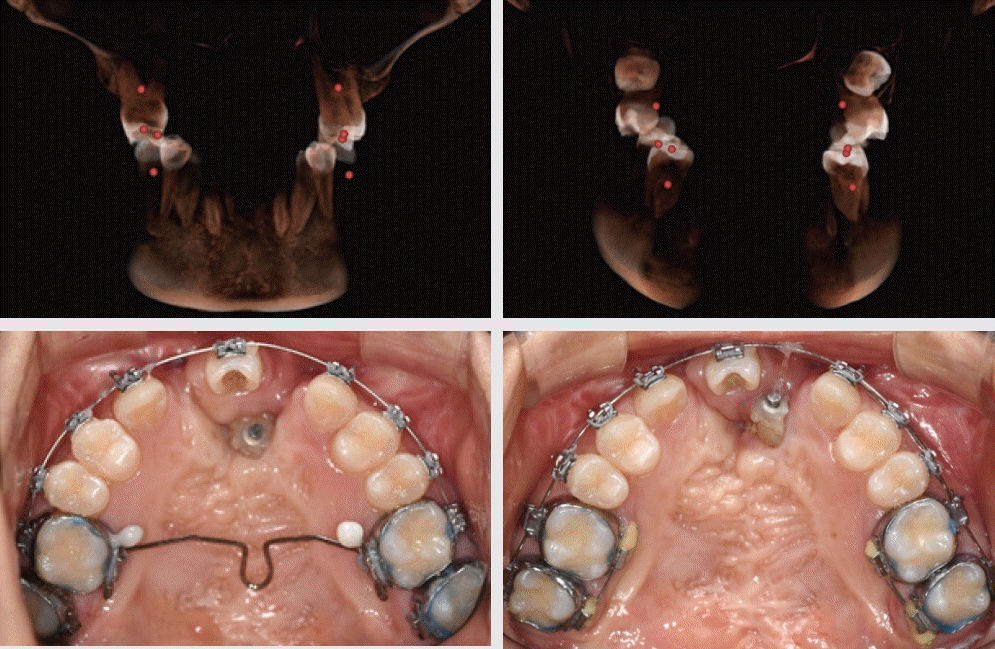

Figure 1.

Unilateral Cleft lip and Palate (Male, 36Y) and Bilateral Cleft Lip and Palate (Female, 20y)

- 구순구개열은 선천성 안면기형 중에서 발생 빈도가 가장 높은 질환으로 알려져 있다[1]. 아시아에서 비교적 높은 발생률이 보고되었고, 우리나라에서는 출생아 1,000 명당 1.8명이라고 보고된 이래[2], 홍과 백은 10년 간의 의료보험 청구자료를 분석하여 1.74명이라고 발표하였다[3], 출산율의 급격한 하락과 인구 절벽이라는 상황에서, 이환된 환자의 지속적이고 포괄적인 생애주기별 치료에 그 어느 때보다 높은 관심이 필요하다.전국민의료보험 치과 보장성 강화 대책의 일환으로, 2019년 3월 구순구개열 치과교정 급여화에 따른 급여기준이 시행된 이래, 2021년 10월 선천성 악안면 기형 질환 중 쇄골두개골이골증(Cleidocranial dysplasia), 두개안면골이골증(craniofacial dysostosis), 크루존병(Crouzon disease), 첨두유합지증(Apert syndrome)에 대하여 급여화의 확대 적용을 거쳐[1], 2022년 11월부터 선천성 악안면 기형 전체로 폭 넓게 적용하게 되었다. 그러나, 급여 대상자 선정 시의 혼란을 최소화하고자, 선천성 기형 환자의 경우에도 (극)희귀질환으로 등록된 자 또는 이력이 있는 자로 한정하였으며, 구순구개열을 동반하는 선천성 악안면 질환의 경우, 두 가지 중 하나만 등록하여도 급여 혜택을 받을 수 있게 되었다[1].내부 통계자료에 근거하여, 경북대학교 치과병원 치과 교정과에 2008년부터 2017년에 걸쳐 내원한 구순구개열 신규 환자는 연간 10명 내외였으나, 2019년의 급여화 이후 급여대상자로 등록된 신규 환자수는 연간 16.6명으로 증가하였다. 앞으로는 선천성 기형 환자들의 신규 내원도 증가할 것으로 예상된다.표준 의료 행위는 출생 이후부터 성장기를 거쳐, 성장완료 이후의 악교정 수술을 포괄하는 생애주기별 교정치료 내용들을 포함하고 있다. 따라서, ‘참1 술전유아악정형장치치료’로부터, ‘참6 고정식 교정장치를 이용한 교정치료’의 순서로 진행하는 것이 일반적이다[1]. 신환의 경우, 생후 3개월 경의 입술 봉합과 1~2세에 행하여지는 구개열 수술과, 전치의 배열, 악궁확장 그리고 견치 맹출 이전에 수행되어야 하는 이차 치조골 이식술(Secondary alveolar bone graft)의 이력을 확인하게 된다. 일반적인 2차 골이식술, 즉 치조열의 골이식 시기는 6~10세로 영구견치의 치근 1/2~2/3 형성 시기를 놓치지 않는 것이 중요하며, 측절치의 맹출을 고려하는 조기 2차 골이식술을 고려할 수도 있다고 알려져 있다[4].그러나, 환자의 첫 교정과 내원 시점에서, 치조골이식술의 이상적인 골이식 시기를 이미 지난 경우이거나, 양측성 구순구개열의 경우에는 골이식을 받아야 하는 이환 부위가 커서, 적기에 이식을 받았다 하여도, 치조열을 회복시킬 충분한 골가교(Bone bridg)가 형성되어 있지 않는 경우도 적지 않다(Figure 1). 좌측은 편측성 구순구개열(Unilateral Cleft Lip and Palate) 환자로 교정치료 이력이 없으며, 치조골 이식술에 대한 설명은 들었으나, 실행한 적은 없는 성인 남자였고, 우측은 적기에 2차 치조골이식술을 받은 이력은 있으나, 치아의 결손 및 치조열이 잔존한 상태로 내원한 양측성 구순구개열(Bilateral Cleft Lip and Palate)의 성인 여성이었다.Hira 빅데이터개방포털(https://opendata.hira.or.kr/op/opc/olapDiagBhvInfoTab3.do)에 따르면, 2019년에서 2022년까지 고정식 교정장치를 부착으로 보험급여 청구된 환자의 33.9%가 20세 이상의 성인이었다. 고정식 교정장치 부착 환자 세 명의 한 명 이상은 성인이었다. 또한 상악 견치가 이미 맹출 된 15세 이상의 환자들에게도 동일한 문제가 발생할 수 있다고 가정하면, 1차 치조골 이식을 받지 못했거나, 추가로 필요한 환자들의 수는 적지 않을 것이다[5].Figure 1에서 보듯이, 구순구개열 환자의 치열에서는 치아 수, 형태 및 맹출 이상이 보고되어 왔다. Baek & Yang [6]은 결손치 56.8%, 과잉치 11,2%, 매복치 18.3%, 왜소치 15.8%의 발생빈도를 보고하였고, Lee & Son [7]은 결손치 26.5%, 과잉치 17.6%, 왜소치 67.6%를 보고하였고, 회전 치아는 64.7%에 달하였다. 따라서, 95% 이상의 구순구개열 환자들에게서 적어도 하나의 치아 기형(Dental anomaly)이 관찰되며, 결손치는 Class III 부정교합을 초래하는 데 기여할 수 있고, 악교정 수술을 계획할 때, 정중선의 일치나 상하악 악궁 조화 시에 치아치조의 불균형으로 인한 방해요소가 될 수 있다[8]. 더구나, 구순구개열 환자는 출생부터 악안면 성장이 진행되는 동안, 일반 교정환자들에 비해 잠재적으로 수복 가능성이 높고, Cleft(열)에 인접한 치아들은 변색되고 법랑질 형성부전이 된 작고 저광화된 경우가 종종 발생한다고 알려져 있다. 이러한 경우 교정용 브라켓 부착이 어려울 뿐 아니라 브라켓 제거 시 수복물에 손상이 생길 수도 있다[8].이러한 일반적인 특성을 더하여, 결정적으로 이차 치조골 이식의 최적 시기를 이미 지난 상태에서 여전히 치조열 부위에 골이식이 가능하도록 치아를 배열하는 것 그리고 여러 방향으로 수축되어 삼각형, 람다, 오메가의 형태를 보이는 상악궁의 형태를 하악궁과 대합이 가능하도록 조정하는 치료는 임상적 난제이다. 특히 오메가 형태의 악궁은, 전치부, 소구치부, 구치부 등 악궁의 부분마다 횡적인 부조화의 양과 방향이 일관되지 않아 단계적인 접근을 수행하여야 한다.따라서, 본 증례 보고는 두 가지 구순구개열 증례, 즉 편측성 및 양측성 구순구개열 (UCLP & BCLP)에서 상악궁의 형태를 재형성하면서, 치조골 이식을 수행한 과정을 소개하고자 한다.